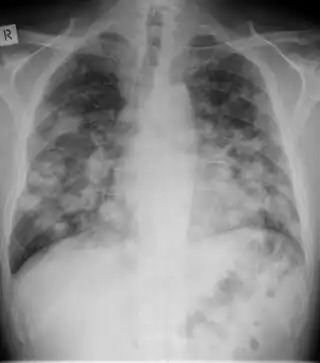

| Chest X-ray: widespread rounded lung nodules throughout both lungs | |

The extent of infection may be seen on X-ray or CT scan. On chest X-ray and CT, pulmonary aspergillosis classically manifests as a halo sign, and later, an air crescent sign.[21]

Chest X-ray: mass overlying the left hilum -

Large cavity mass lesion seen right upper lung -

CT scan lungs: multiple lung lesions with ground-glass opacity suggesting haemorrhage